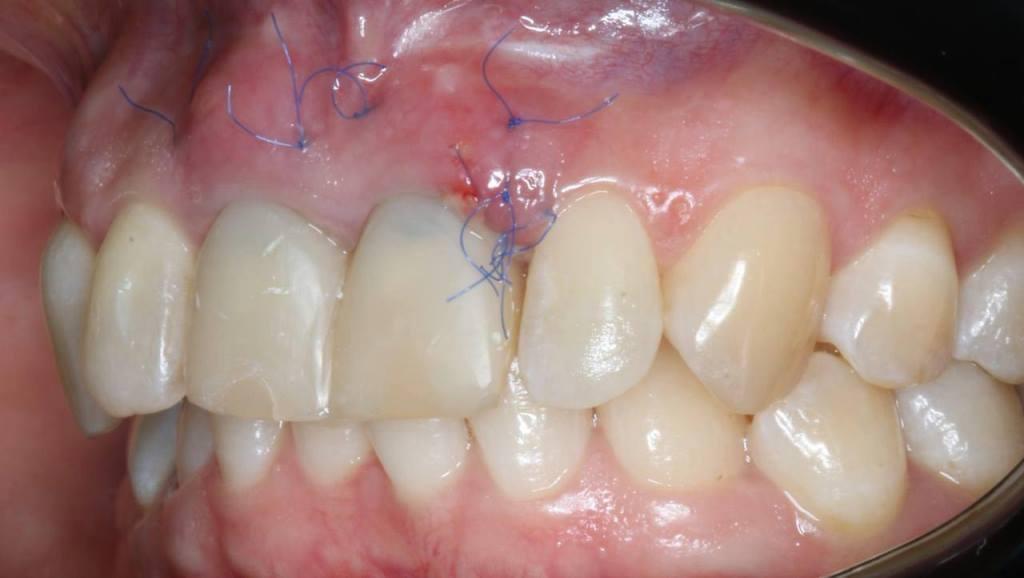

Фото 3, 4, 5.

Очень важно во фронтальном отделе корректное параллельное расположение имплантатов во всех трех плоскостях.